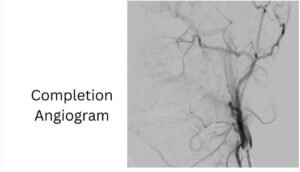

ومن جانبه، ذكر الدكتور احمد كمال المدير التنفيذي للمستشفيات الجامعية، أنه تم تجهيز وحدة القسطرة على الفور، حيث نجح الفريق الطبي في غلق التمدد الشرياني باستخدام حلزونات دقيقة عبر القسطرة التداخلية، مما أسهم في السيطرة الكاملة على النزيف دون الحاجة إلى جراحة تقليدية، وتقليل احتمالات المضاعفات.

وأكد الدكتور محمد زاكي رئيس قسم الأشعة، بأن الحالة خرجت في وعي كامل مع استقرار تام في العلامات الحيوية، مؤكدًا أن هذا التدخل يمثل نموذجًا للتنسيق السريع بين الفرق الطبية في الحالات الطارئة.